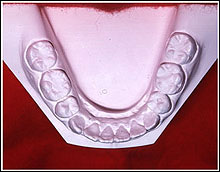

INTRAORAL Model